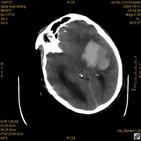

病人杨XX,男,青云街道办事处路踏泉村,住院号51666,CT号:104770。病人因“高血压脑出血”在新泰市人民医院住院治疗5天,治疗效果不佳转入我院,复查CT示左基底节血肿,病人昏迷状态,给予血肿清除术,术后2天复查CT,血肿完全清除,病人恢复好,治疗效果满意。附病人术前术后CT片资料如下。

术前CT

术前CT1 术前CT2 术前CT3 术前CT4